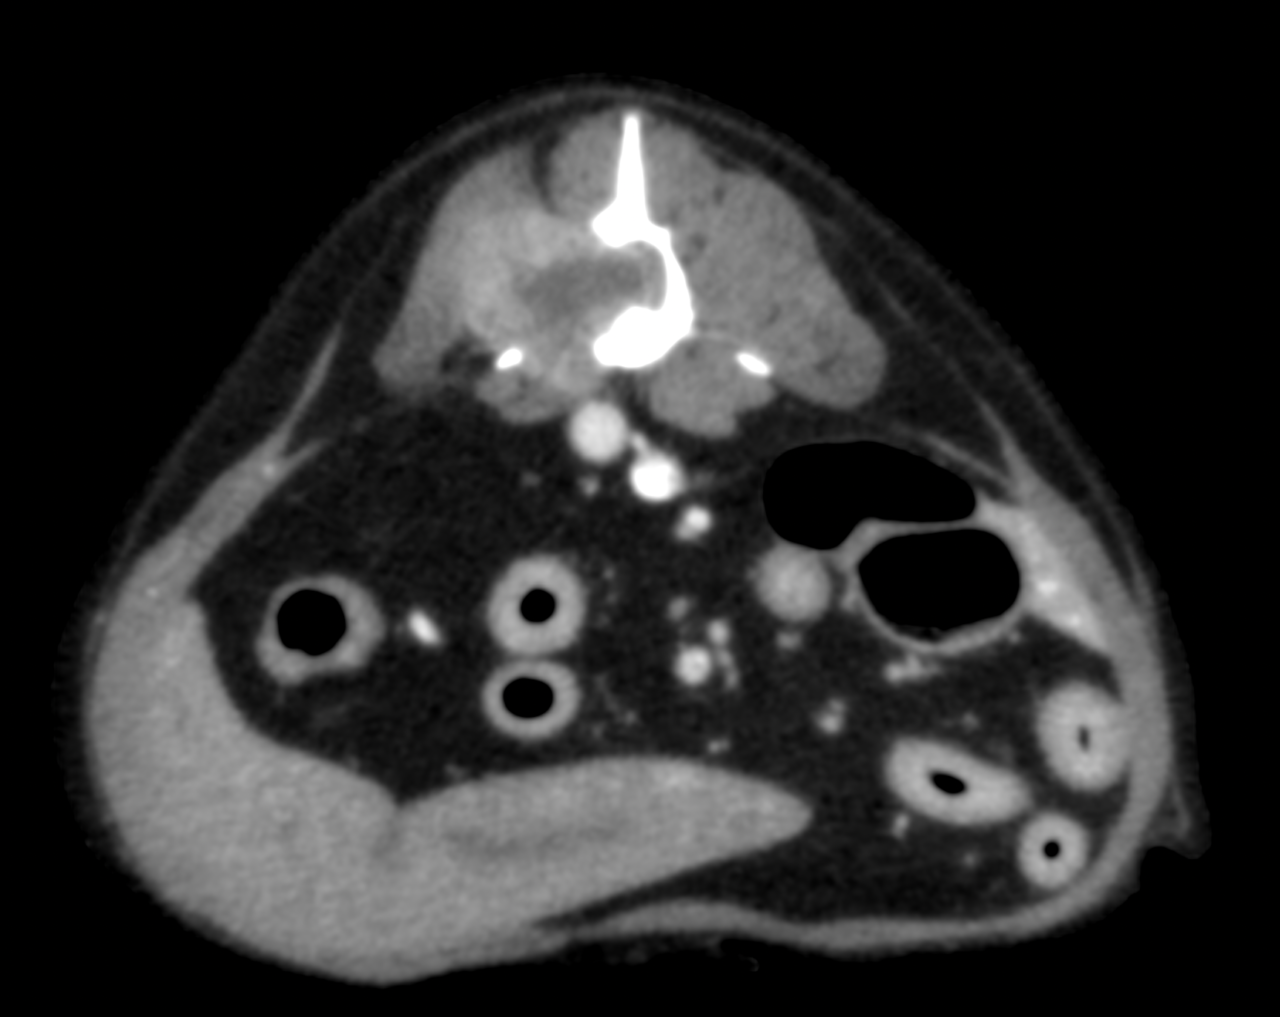

10歳のワンコが後肢フラツキの精査のため、かかりつけの動物病院より画像診断と治療のために紹介受診されました。CT/MRI検査では第3腰椎の左側から脊柱管内に重度に浸潤し、脊髄の90%以上を圧迫する占拠性病変が確認されました。また椎体にも骨融解像が確認されました。姑息的ではありますが、腫瘍摘出により除圧することで神経学的機能回復に期待することと、今後の病期の進行に伴い椎体の不安定性が懸念されたため、2.0mmのTitanium Locking Plateを2枚用いて部分的にスタッキングさせると同時に4本のLocking Screwを用いて椎体固定術を実施しました。脊柱管内に浸潤し、脊髄を圧迫していた腫瘍はほぼ完全な摘出が可能となりました。術後すぐに歩行可能となり、良好な機能回復が得られています。今後は摘出した腫瘍の病理検査により追加の治療を決定します。